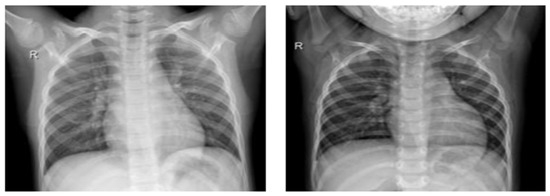

Samples of normal X-ray images [4].

The collection of chest X-rays from patients with COVID-19 was sourced from an open-access data repository. This database encompasses a comprehensive set of chest X-ray images, comprising 1184 images of individuals confirmed as COVID-positive and 1319 images of individuals without COVID-19 diagnosis. Our investigation is fundamentally grounded in this database, which organizes chest radiography images into two distinct categories, as visually represented in Figure 4. The categories include individuals who exhibit no infection and individuals who have been diagnosed with COVID-19. To facilitate our research and maintain robust evaluation practices, we randomly partitioned this dataset into two distinct subsets. The division allocated 80% of the images for the training phase, enabling model development and refinement, while the remaining 20% were reserved for testing, serving as an independent validation dataset. This partitioning strategy ensures a reliable assessment of our models and their generalization capabilities.

Figure 4.

Sample of infected X-ray images [4].